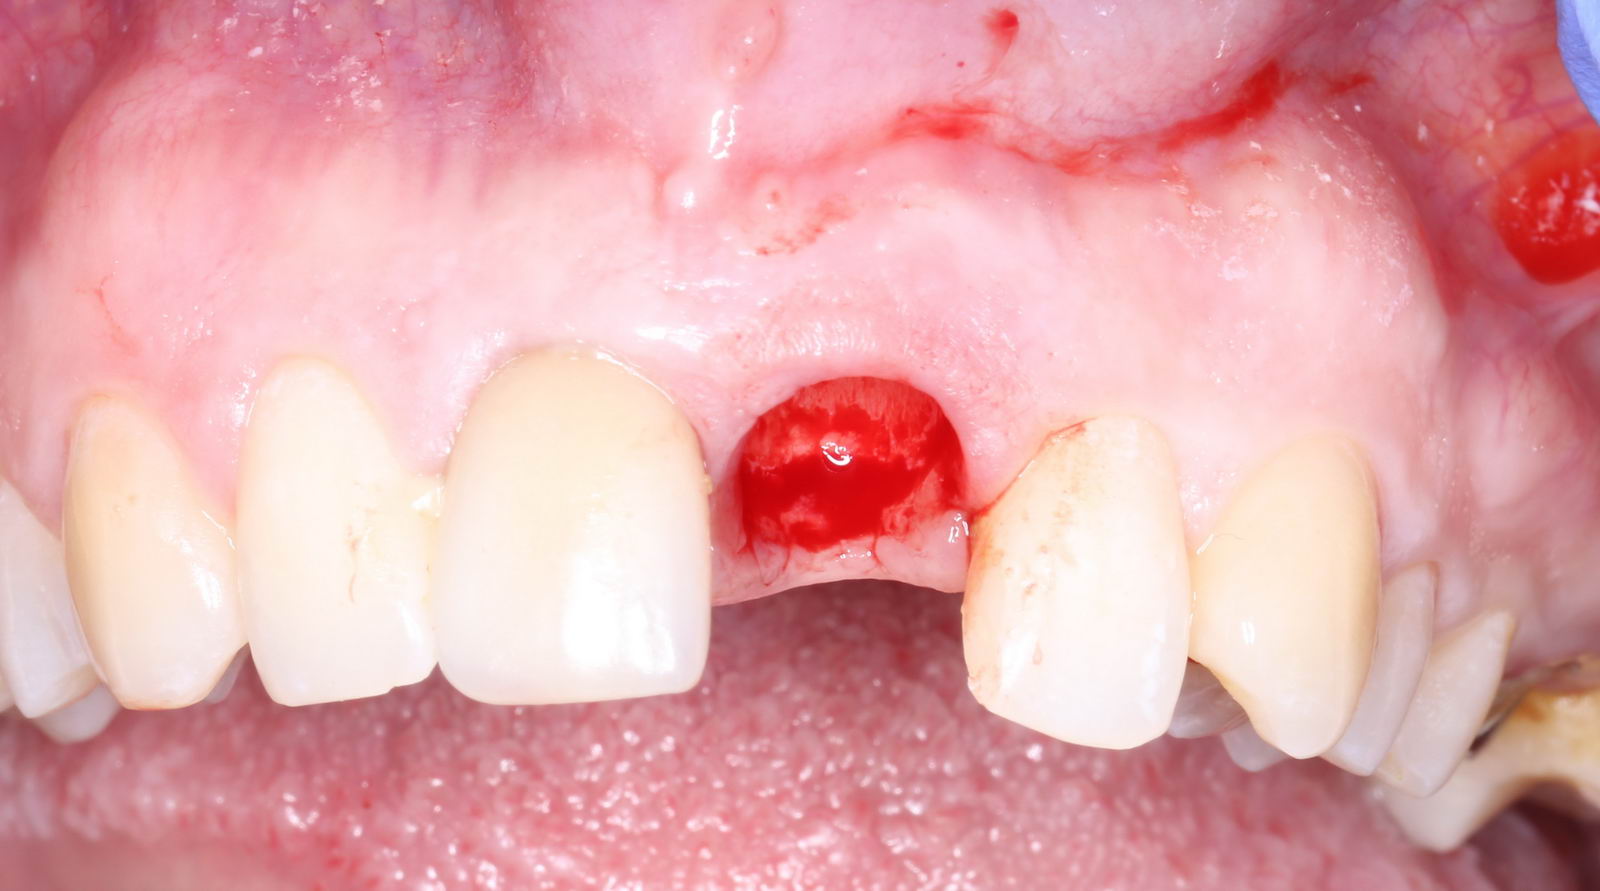

Всё чаще задавая такие вопросы, мы пришли к так называемой методике «немедленной имплантации» — установке имплантата в лунку только что удалённого зуба.

Выглядит это так: